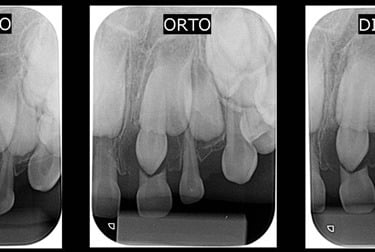

RADIOGRAFIA PERIAPICAL

TÉCNICA DE CLARK